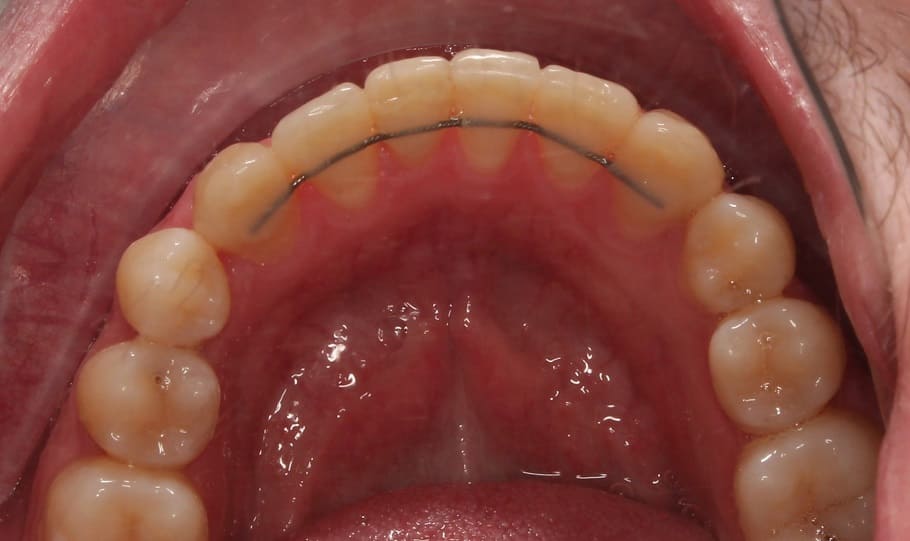

Лечение на самолигирующей брекет-системе Н4. Ортодонтическое лечение заняло 2 года.